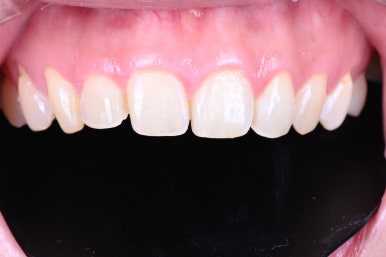

앞니가 약간 짧은 느낌이 있습니다.

짧은 앞니는 어른보다는 아이같은 느낌을 주기 쉽죠.

그리고 전체적으로 약~간 네모난 느낌을 가지고 있는 것 같습니다.

하지만 또 엣지있을 정도의 네모난 치아 모양은 아니었어요.

왼쪽이 위 앞니, 오른쪽이 아래 앞니 사진입니다.

분명히!! 가지런한 치아는 맞습니다.

일단 가운데 두 치아 - 대문니가 모양이 다릅니다.

노란색 점선으로 된 부분을 보시면 차이를 바로 느끼실 수 있어요.

요기서 오는 비대칭 느낌을 바로 잡아야 했고,

파란색 화살표를 보시면, 대문니 옆에 있는 작은 앞니의 크기가 달라보입니다.

역시나 비대칭 느낌을 주는 포인트...

빨간색 화살표를 보시면, 잇몸의 길이가 다르죠?

이러한 작은 요소요소가 모여서 비대칭이 더욱 돋보이게 만드는 상태셨어요.

치아의 색상도 좀 더 밝아지길 희망하셨습니다.

다만, 자연스러운 색상을 원하셨어요.